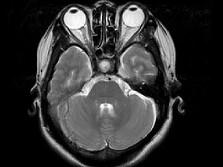

女,41岁,阵发性头痛伴恶心、呕吐20余天,CT影像如图,最可能的诊断为 ( )

• A.双侧筛窦息肉

• B.双侧筛窦息真菌感染

• C.双侧筛窦过敏性炎症

• D.双侧筛窦炎

• E.双侧筛窦未见明显异常

答案: D